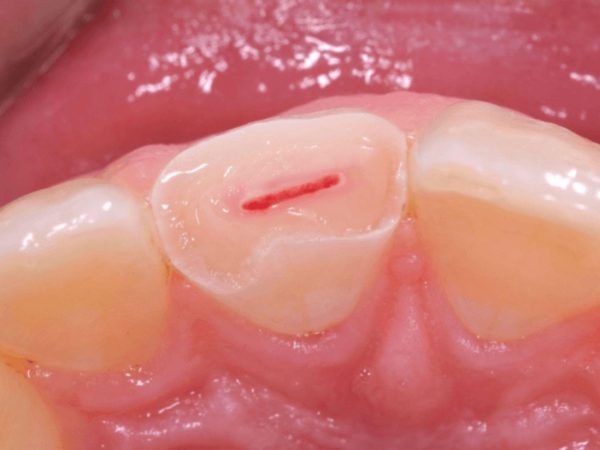

Răng bị vỡ, mẻ lớn lộ buồng tủy

Khi răng bị chấn thương hoặc mẻ sâu, phần buồng tủy có thể bị lộ ra ngoài. Điều này khiến dây thần kinh bên trong bị kích thích mạnh, dễ nhiễm khuẩn và gây đau nhức kéo dài.

Nếu chỉ bọc sứ mà không lấy tủy trong tình trạng này, vi khuẩn sẽ tiếp tục phát triển trong buồng tủy kín, gây viêm tủy hoặc áp xe quanh chóp răng sau đó.

Do đó, bác sĩ sẽ tiến hành:

- Lấy tủy răng để loại bỏ mô tủy tổn thương,

- Trám bít kín ống tủy,

- Sau đó phục hình mão sứ để bảo vệ cấu trúc răng và khôi phục hình dáng ban đầu.